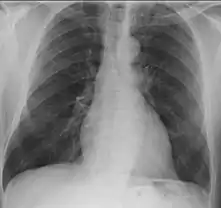

- Lungs: pulmonary nodules (referred to as "coin lesions"), infiltrates (often interpreted as pneumonia), cavitary lesions, bleeding in the lungs causing a person to cough up blood, and rarely bronchial stenosis.

- Lungs: abnormal chest X-ray with:

- nodules,

- infiltrates or

- cavities